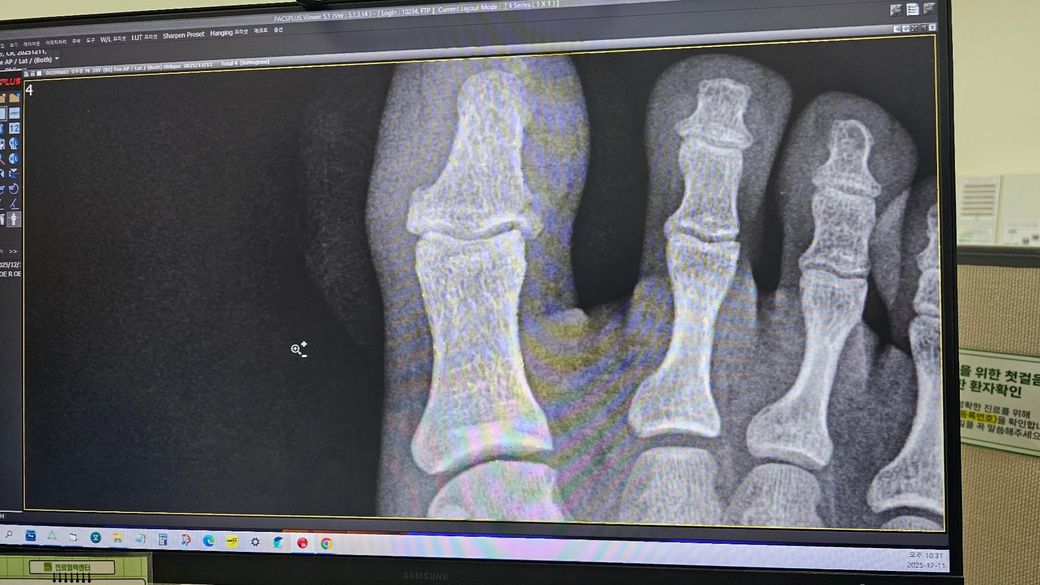

• 2번 째 사진

12월 11일밤 원판 20kg가 엄지발가락에 떨어져서 응급실 내방 개방성골절을 확인했고 후

12월 12일 금요일 오전 전문병원에서 핀을 박고 발톱 부위를 꿰맸습니다.